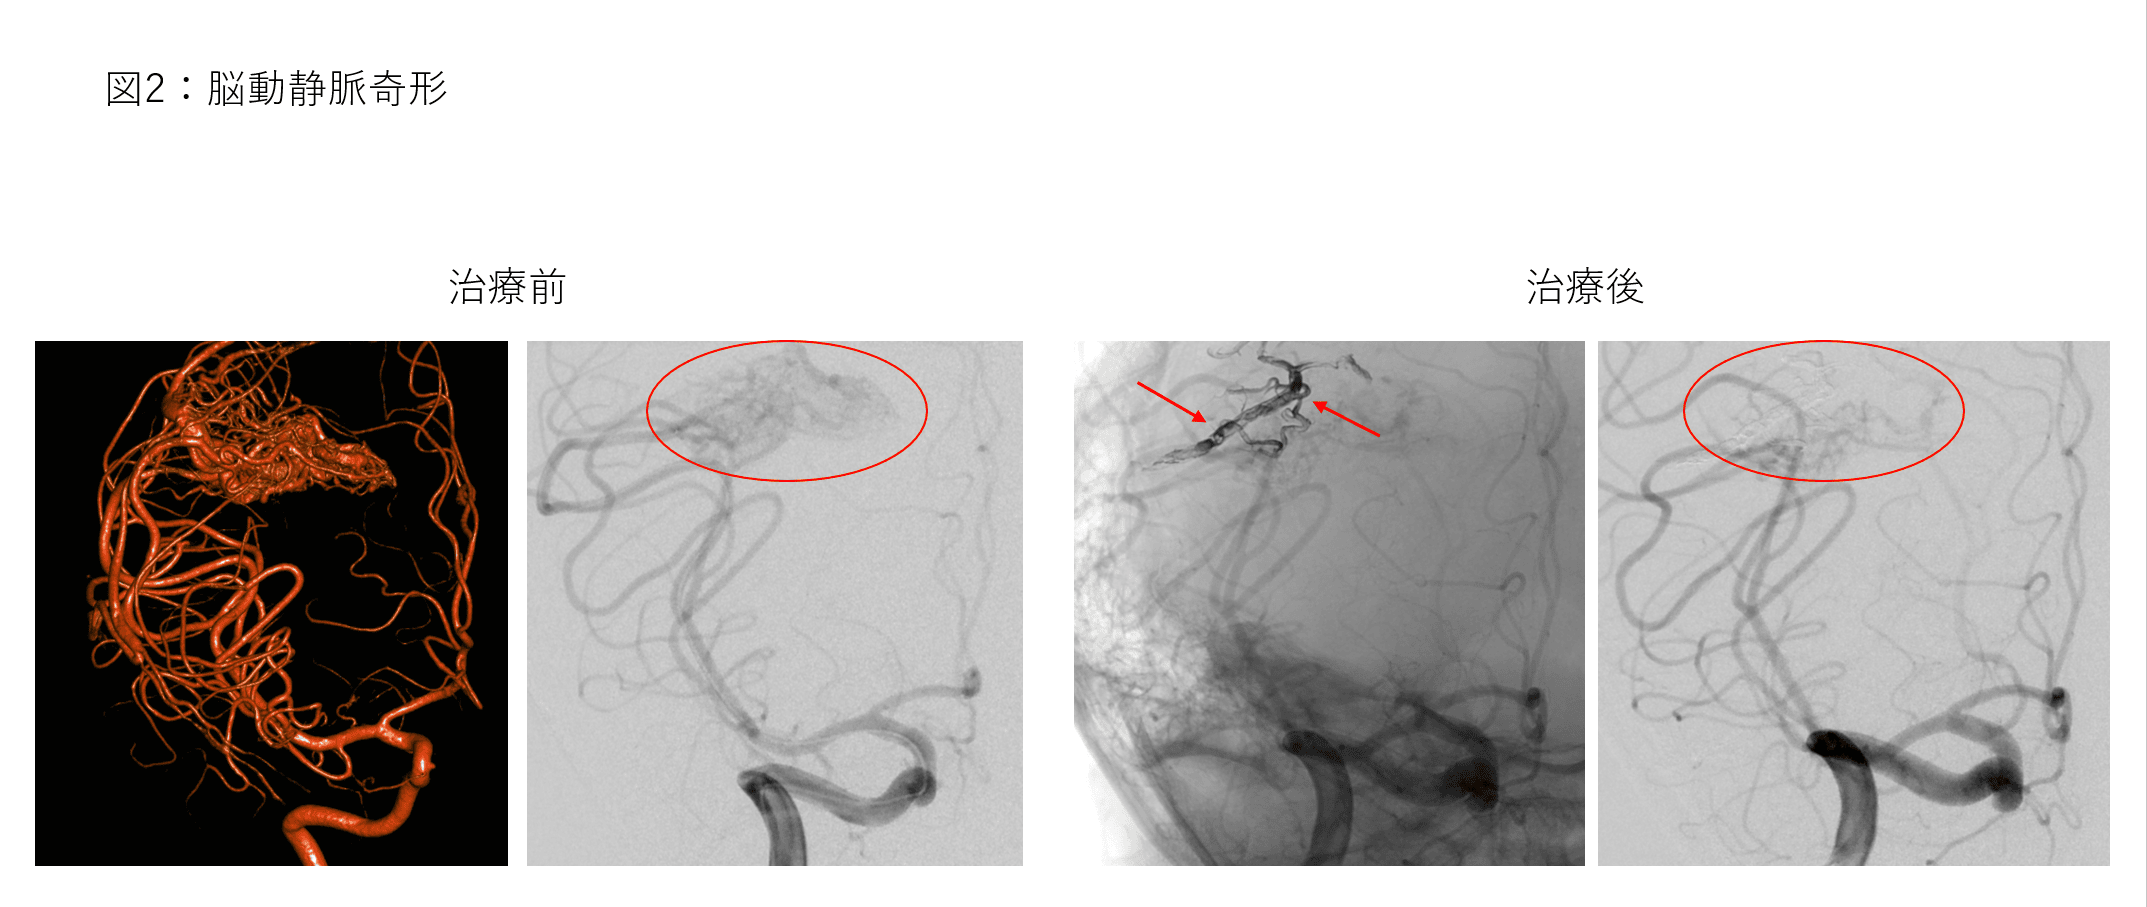

動静脈奇形、硬膜動静脈瘻などの稀少疾患

脳または脊髄における脳動静脈奇形、硬膜動静脈瘻は、病気になる患者さんの数が少なく稀少疾患に該当します。治療方法は、外科手術、放射線治療、脳神経血管内治療と複数あり、疾患の状態によってこれらの治療方法を組み合わせて行います。 脳神経血管内治療は、動静脈奇形、硬膜動静脈瘻の本体およびそれに向かう血管を塞栓物質で閉塞します。特に液体塞栓物質(Onyx、NBCA)はその効果が高いため、積極的に使用しています(図2)。 治療手技だけでなく全体を見据えた治療方針など診療に経験を要する疾患でありますが、それに該当する治療経験を有すると自負しています。